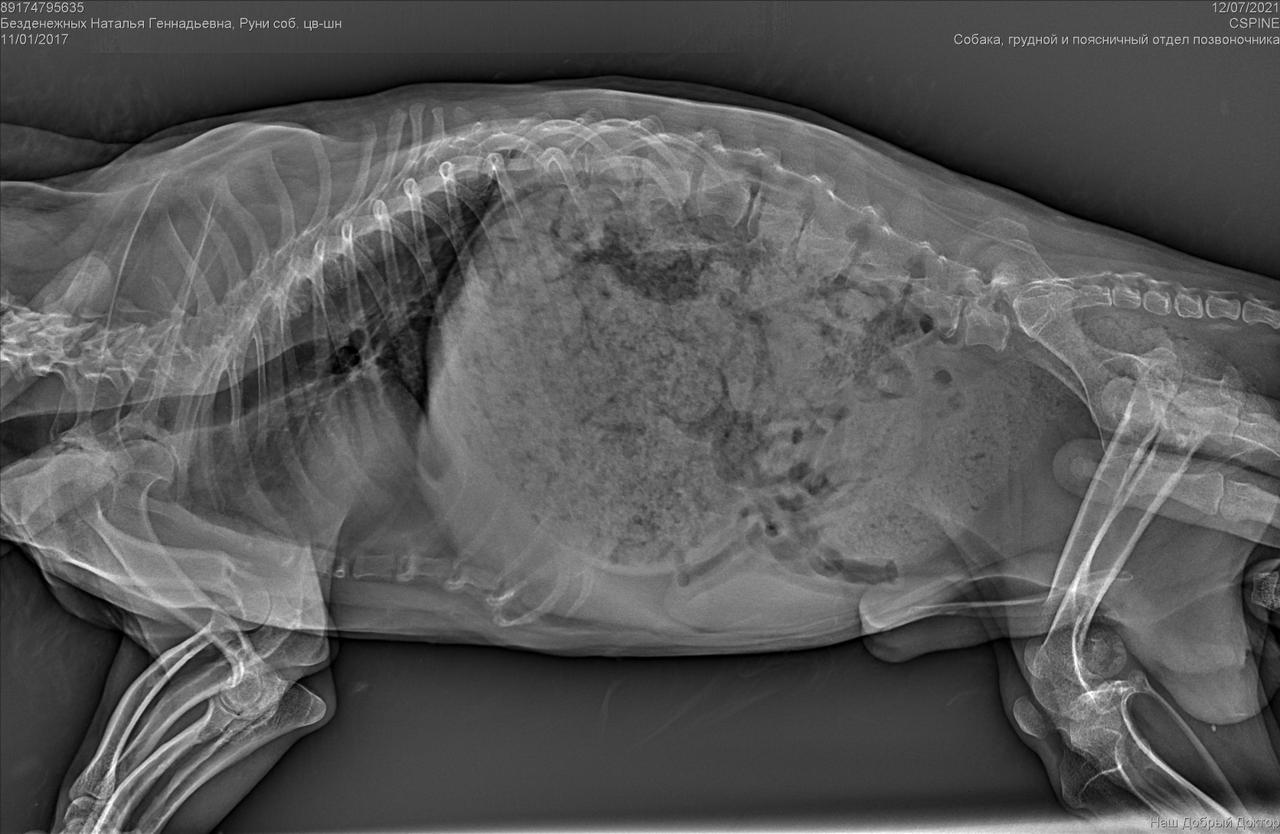

С собакой сегодня поедут в клинику. Передержать и полечить смогут. Попросила в клинике посмотреть клеймо и посканировать ип.

ПОнадобится наша помощь с оплатой лечения и поиском дома.